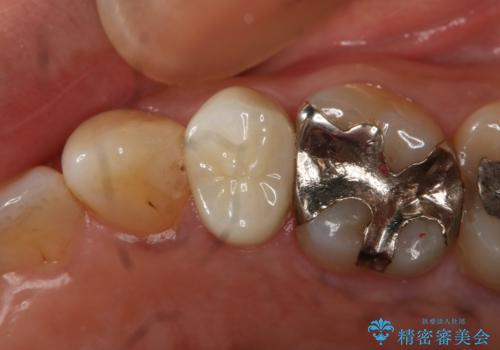

- 左下大臼歯の歯肉に腫れと痛みが繰り返し起こっているので治療を希望し来院された患者様です。

既に治療されている歯でしたが根尖部に病巣が確認出来たので、精密根管治療とクラウンの再治療が必要と判断されました。

精密根管治療を行なったことで病巣は消失し、腫れや痛みは再発することなく経過は良好です。

被せ物はフルジルコニアクラウンを選択されました。